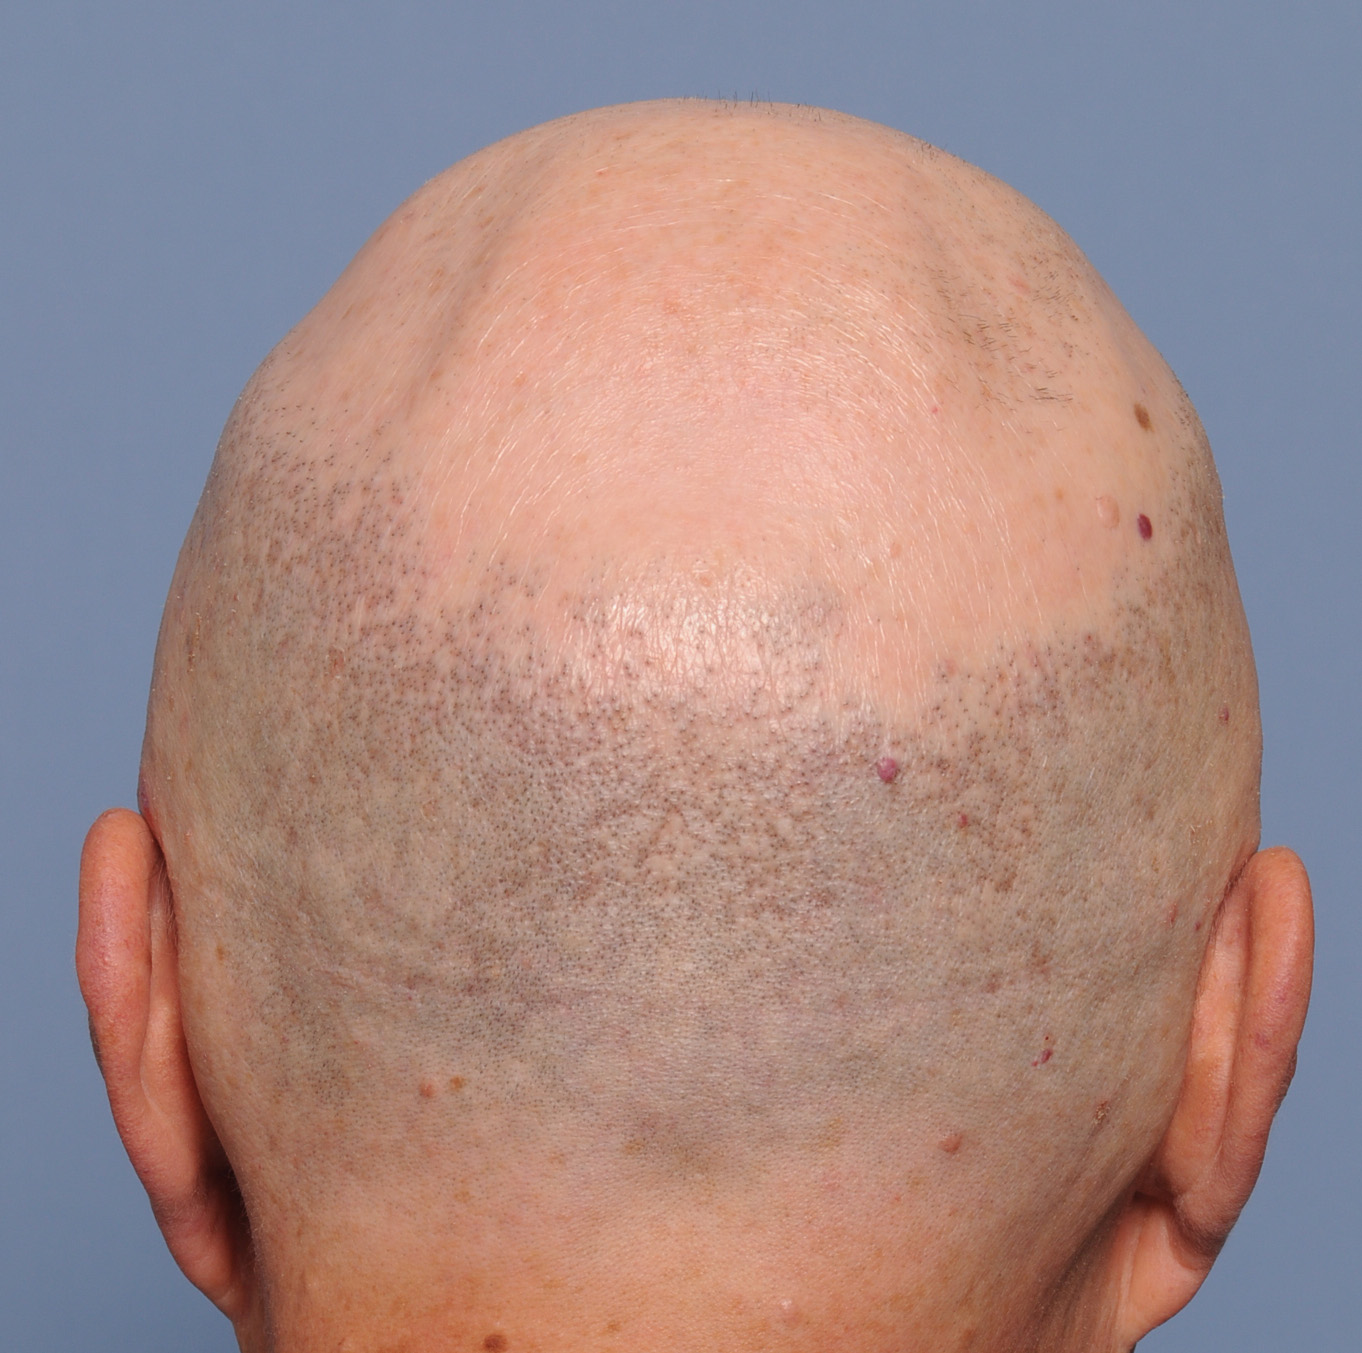

Patient 100

Desire for reshaping of an asymmetric flat back of the head in a shaved head male.

A combined back of the head reshaping procedure was done with a custom skull implant, sagittal ridge reduction and a right temporal muscle reduction.

Desire for reshaping of an asymmetric flat back of the head in a shaved head male.

A combined back of the head reshaping procedure was done with a custom skull implant, sagittal ridge reduction and a right temporal muscle reduction.